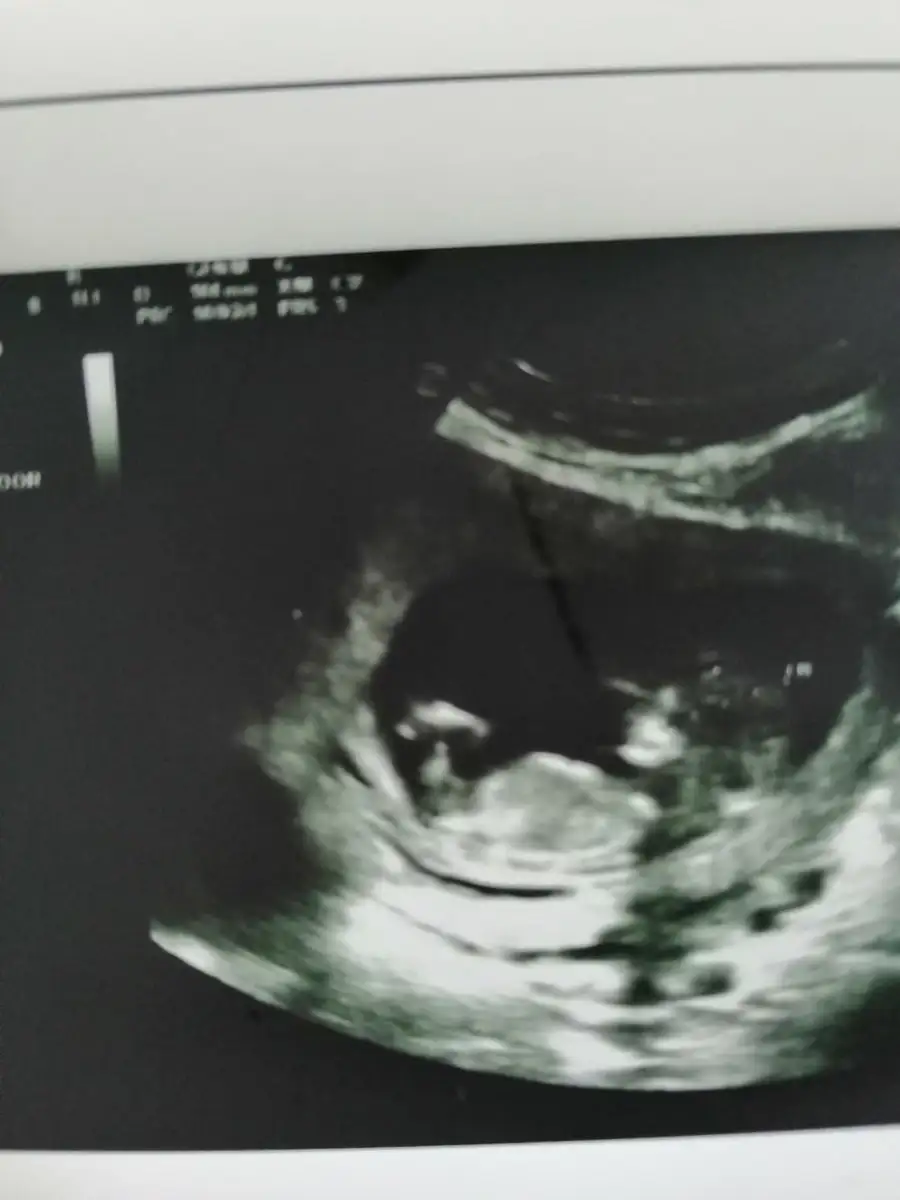

İyi canım şükür, 12+2 görünüyor. İkili testi de yaptırdık,ense kalınlığı normal kan sonucu 1 haftaya çıkar dedi.

Cinsiyeti belli degil. Bacak bacak üstüne atmıştı ve arasında kordon vardı:KK45: doktor dürttü ama fayda etmedi :KK48:

Bu da fotosu :KK53:Eki Görüntüle 2219948